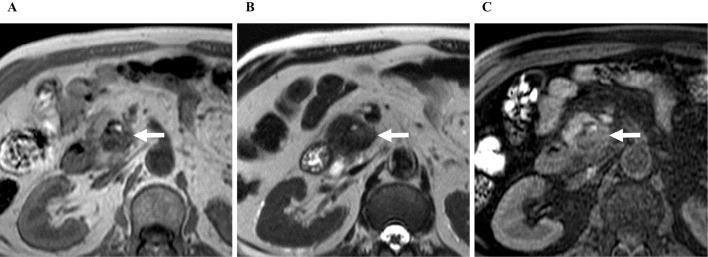

Osteoclast-like giant cell-type (OCGC) anaplastic carcinoma is a rare variant of pancreatic ductal adenocarcinoma, and its imaging characteristics and progression pattern have not been fully clarified. The patient was a 73-year-old man who had been incidentally found to have a pancreatic head tumor. Computed tomography demonstrated a 3-cm marginally enhanced mass at the pancreatic head, continuing toward the duodenum. Diffusion-weighted magnetic resonance imaging showed a retained diffusion capacity. Duodenoscopy revealed a 1.5-cm polypoid lesion, covered by a dirty coat, near the major papilla. Surgical material revealed OCGC pancreatic anaplastic carcinoma protruding to the duodenum, accompanied by multiple hemorrhagic foci and hemosiderin precipitations.

破骨细胞样巨细胞型(OCGC)间变性癌是胰腺导管腺癌的一种罕见变体,其影像学特征和进展模式尚未完全阐明。该患者为一名73岁男性,偶然发现胰头肿瘤。计算机断层扫描显示胰头有一个3厘米的边缘强化肿块,延伸至十二指肠。扩散加权磁共振成像显示扩散能力保留。十二指肠镜检查发现主乳头附近有一个1.5厘米的息肉样病变,表面有污秽物覆盖。手术材料显示OCGC胰腺间变性癌突出至十二指肠,伴有多个出血灶和含铁血黄素沉着。